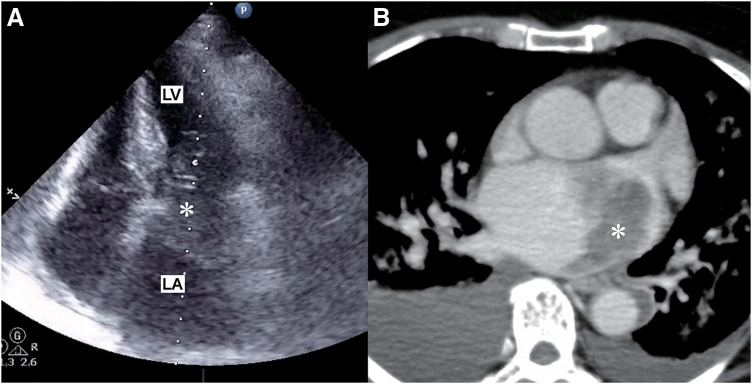

Case presentation: A 67-year-old woman with no prior history of cardiac tumors was admitted for dyspnea and was found to have a 60 mm tumor in the left atrium. Despite initial resection, the tumor recurred twice, and a subsequent pleural mass biopsy revealed metastasis of myxofibrosarcoma. Retrospective analysis confirmed that the pathological findings of all the resected tumors were consistent with myxofibrosarcoma. Chemotherapy with doxorubicin was initiated, but severe side effects led to its discontinuation. The tumors continued to grow, causing significant pain, and she passed away a year later.